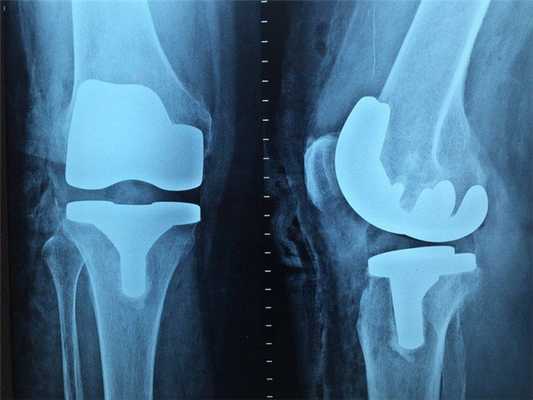

Классический рентген по-прежнему остаётся важным методом для диагностики самых разных заболеваний. Например, маммография (рентгеновское исследование молочных желез) - лучший способ скрининга рака молочной железы. Возможности КТ в выявлении злокачественных и воспалительных процессов в этом органе существенно ниже.

Доза радиологического облучения при КТ значительно выше, чем при рентгеновском исследовании, не стоит «бить из пушки по воробьям». К примеру, при подозрении на перелом или при первичном обращении с болью в суставах предпочтительнее сделать рентген.

Что покажет рентген

Рентген - это самый широко доступный тип обследования. В Санкт-Петербурге его можно сделать быстро на платной или бесплатной основе как в частных, так и в государственных клиниках и больницах. Основная задача рентгенографии - дать общее представление об изменении структуры органов и костной ткани. С помощью рентген-аппарата врач может хорошо визуализировать:

- инородные тела;

- переломы;

- воспаление легких;

- рак молочной железы;

- туберкулез.

Основное преимущество рентгенографии заключается в том, что это быстрый и дешевый метод сканирования. Однако по точности и диагностической ценности он безусловно уступает как УЗИ, так и таким высокотехнологичным методам исследования, как МРТ и КТ.

В основе физики работы рентген-аппарата лежат просвечивающие способности рентгеновских лучей. Получение плоского двухмерного изображения основано на ослаблении рентгеновского излучения при его прохождении через различные ткани. При рентген-сканировании пучок излучения, проходя через ткани организма, которые обладают различной плотностью, рассеивается и тормозится. Таким образом, на пленке возникают изображения разной степени интенсивности. Лучевая нагрузка при рентгенографии небольшая, но она всегда есть и может составлять от 0,1 до 1 мЗв. Поэтому рентгенография запрещена для беременных женщин, а здоровому человеку рентген можно делать 1- 2 раза в год.

Кроме дозы облучения у рентгеновского сканирования есть один существенный диагностический недостаток - плоская картинка. Поскольку рентген изображения - это тень ткани на пленке, объемно оценить органы и структуры человеческого тела с помощью рентгена не получается.

Рентген

Наиболее старый и привычный метод визуализации человеческого тела. Применяют рентген повсеместно, от хирургии до стоматологии. Метод прост и понятен: человека облучают особыми лучами, которые легко проходят сквозь мягкие ткани и задерживаются в твёрдых. Благодаря этому принципу, на фотоплёнку или датчик, расположенные на противоположной от источника лучей стороне, передаётся изображение, а в распоряжение врача попадает рентгенография или рентгеноскопия.

Главные плюсы такого обследования: быстрота и стоимость. Рентгеновскими аппаратами оснащены практически все больницы, процедура проходит быстро и стоит недорого.

Главные минусы: облучение и качество изображения. При проведении рентгенографии пациент облучается, а картинка получается двумерной. Врач с трудом может разглядеть внутренние органы по отдельности, поскольку их тени перекрывают друг друга. Также невозможно детально разглядеть хрящевую ткань и мозг. Хрящи практически не задерживает лучи, мозг надёжно закрыт черепной коробкой. Для их исследования рентгенография не подойдёт.

Наиболее эффективно будет проводить рентгенографию при повреждениях костей, суставов и зубов.